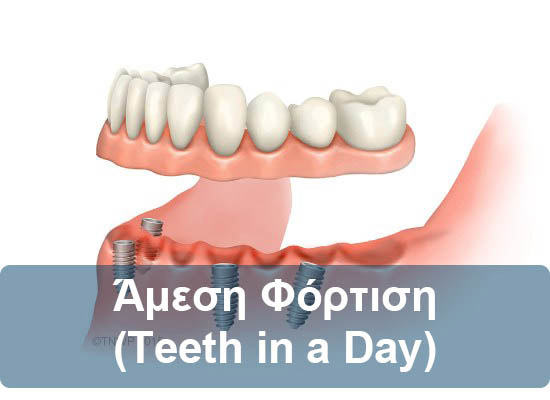

Εξαγωγή, άμεση εμφύτευση και άμεση φόρτιση